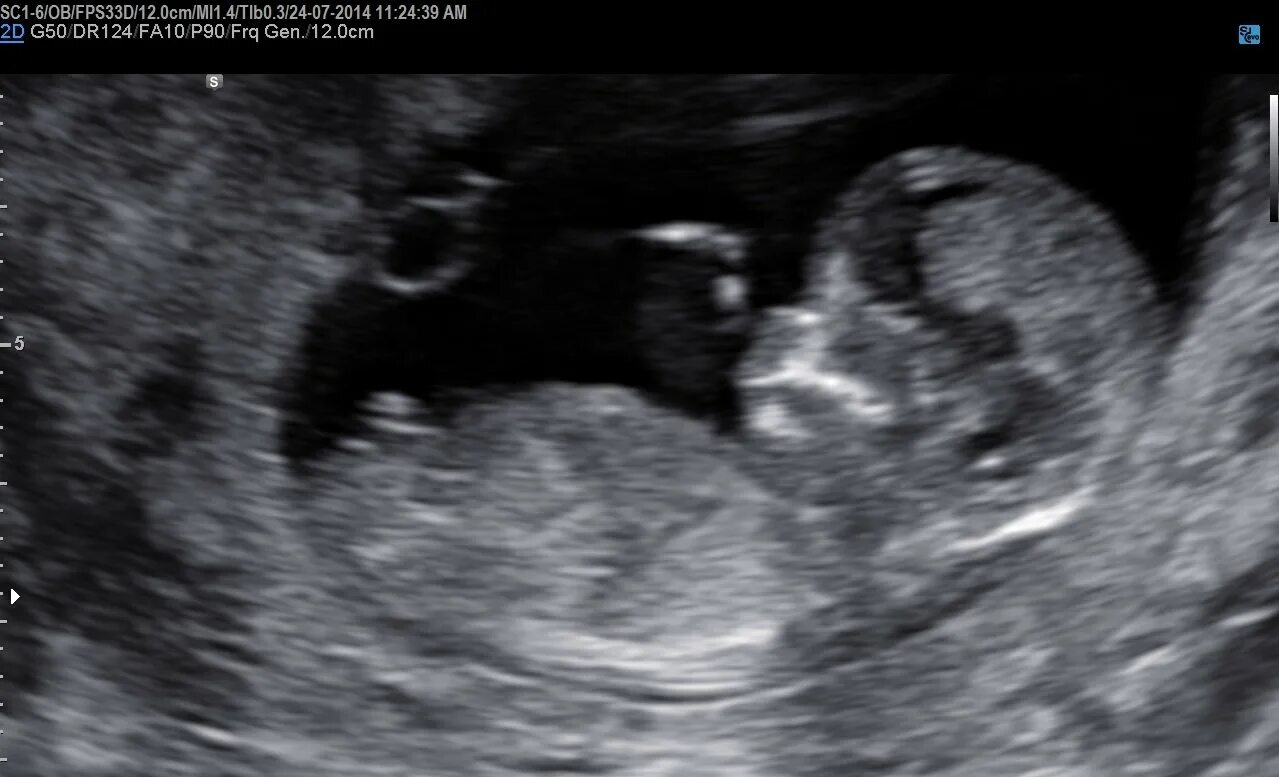

Малыш на первом скрининге